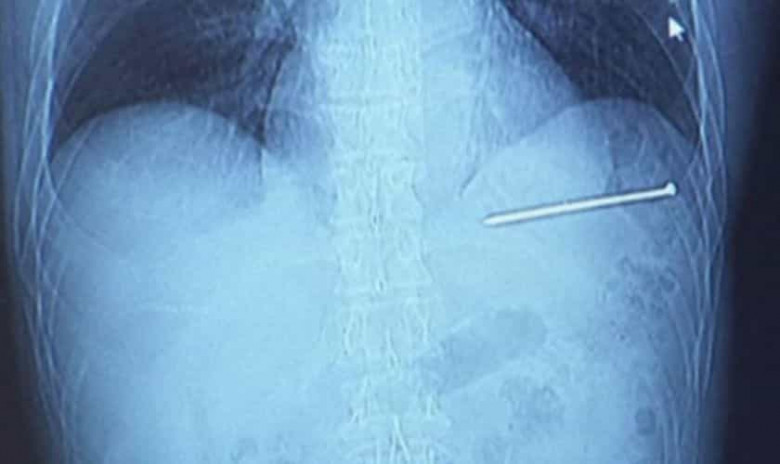

Տղամարդը մեխի ատրճանակով միամիտ կրակել է սրտի վրա ու այդ վիճակում մեքենայով հիվանդանոց հասել

BlogNews.am/ԱՄՆ Վիսկոնսին նահանգում բնակվող Դուգ Բերգեսոնը գրեթե ավարտում էր տան ներսում գտնվող բուխարու շուրջ ամրացրած շրջանակների վերանորոգման աշխատանքները, երբ մեխի ատրճանակով հանկարծ կրակոց ստացավ սրտի հատվածում։

«Կրունկներիս վրա կքանստած էի, այնպես ստացվեց, որ մեխի ատրճանակն ուղղվեց դեպի ինձ։ Հանկարծ այն մեխ արձակեց սրտիս վրա»,- պատմել է Բերգեսոնը։

Մոտավորապես 9 սանտիմետր երկարությամբ մեխն ուղիղ մտել է նրա սիրտը, այն էլ՝ բավականին մեծ արագությամբ։

«Այն անգամ չցավեց։ Ընդամենը միջատի խայթոցի պես ցավ զգացի, հետո նայեցի ներքև, սակայն ոչինչ չտեսա»։ Այդ վիճակում Բերգեսոնը նստել է մեքենան և այն վարելով շտապ հասել հիվանդանոց, որը 20կմ հեռավորության վրա է գտնվում։ Սակայն տեղի բժիշկներն էլ նրան անհապաղ այլ հիվանդանոց տեղափոխեցին, որպեսզի վիրահատեն։

Բարեբախտաբար, մեխը չի դիպչել սրտի գլխավոր զարկերակին, սակայն մխրճվել է դրա անմիջապես կողքը՝ ընդամենը մեկ թղթի հաստության չափ հեռավորության վրա։